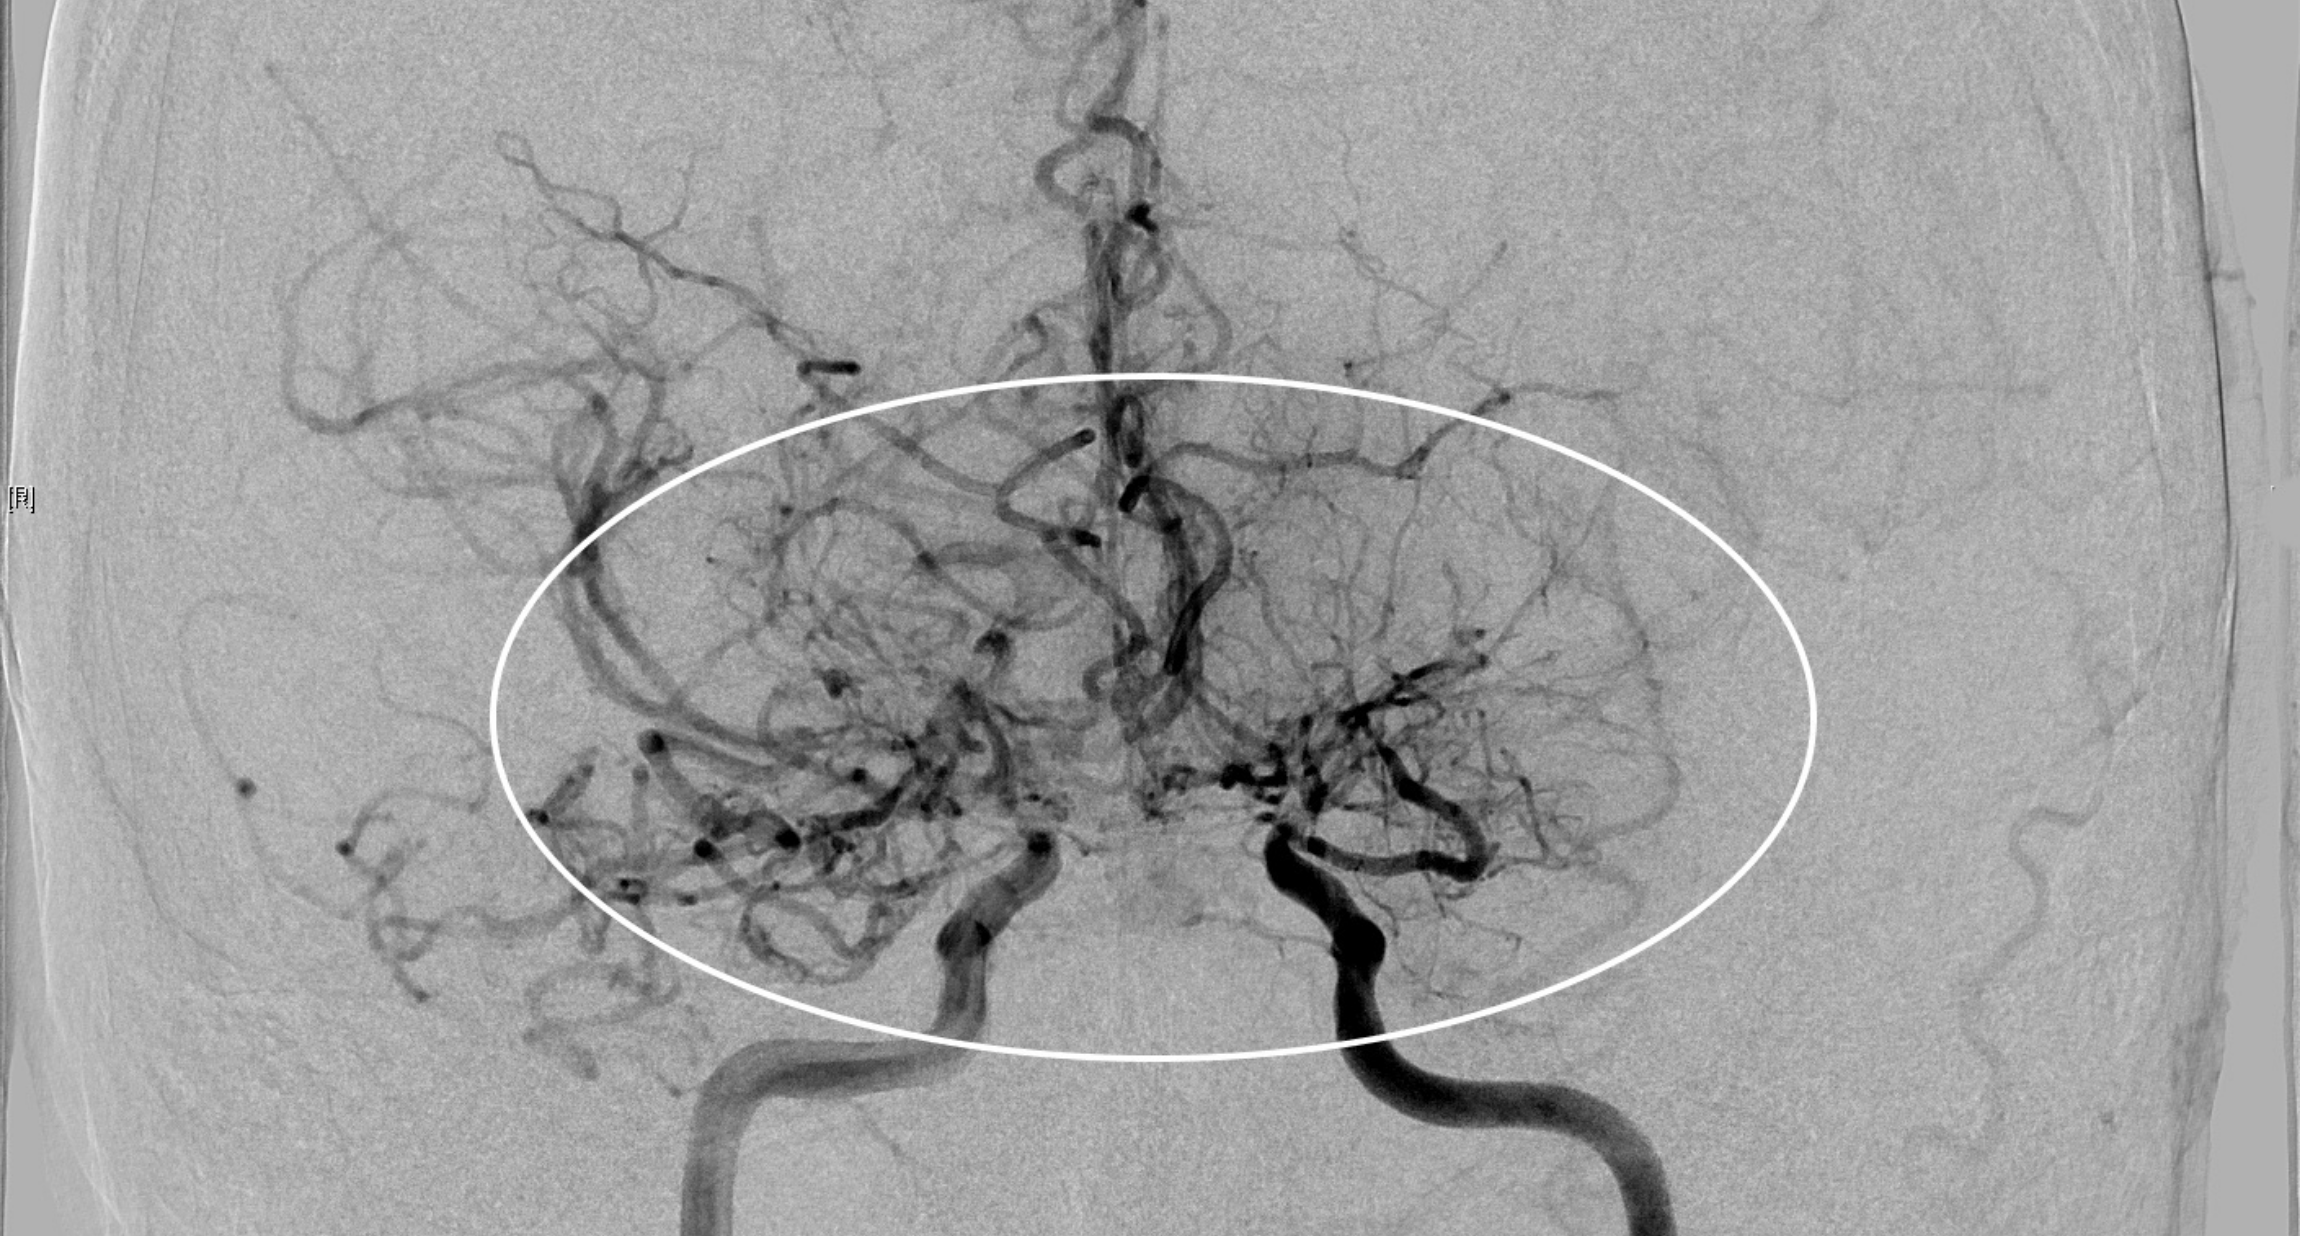

Edyta Fischer ist an Moyamoya erkrankt, einer seltenen Gefäßerkrankung, die zu Verschlüssen der großen Hirnarterien führt. In der Folge bilden sich kleine Umgehungs-Blutgefäße, die in der Angiografie – der radiologischen Darstellung von Gefäßen – wie eine Nebelwolke aussehen. „Nebel“ bedeutet im Japanischen „moyamoya“. Dort ist die Krankheit verbreiteter als in Europa. Patientinnen und Patienten haben ein erhöhtes Schlaganfallrisiko, da die Blutzufuhr zum Gehirn nicht ausreicht oder es zu Hirnblutungen kommen kann. Doch davon ahnt die Mutter von zwei Söhnen nichts, als sie an Pfingsten 2023 in das Krankenhaus in Uelzen eingeliefert wird und ihre Odyssee durch die Kliniken beginnt. „Ich habe vorher überhaupt nichts gehabt, ich war topfit und habe gedacht, das legt sich wieder“, erzählt sie.

Wie alle seltenen Erkrankungen ist Moyamoya schwierig zu diagnostizieren. Kleinere Krankenhäuser sind für die multimodale Spezialdiagnostik nicht ausgelegt, dafür gibt es spezielle Kompetenzzentren – insgesamt drei in Deutschland. Neben einer umfassenden Angiografie der hirnversorgenden Gefäße, hochauflösenden MRT-Sequenzen und einer funktionellen MRT gehört auch eine PET-CT zur diagnostischen Abklärung bei Moyamoya dazu. „Diese Untersuchungen können nur an ganz wenigen Orten in Deutschland durchgeführt werden, weil man ein spezielles technisches Setup benötigt und auch sehr hohe Expertise bei der Bewertung der Ergebnisse. Nur durch die Zusammenschau aller Untersuchungen können wir mit Sicherheit die Gefäßbereiche identifizieren, deren Durchblutung mit einer Bypass-Operation wiederhergestellt werden muss“, erläutert Prof. Dr. Constantin Roder, Leiter des Zentrums für Moyamoya und assoziierte Angiopathien der Uniklinik Tübingen.